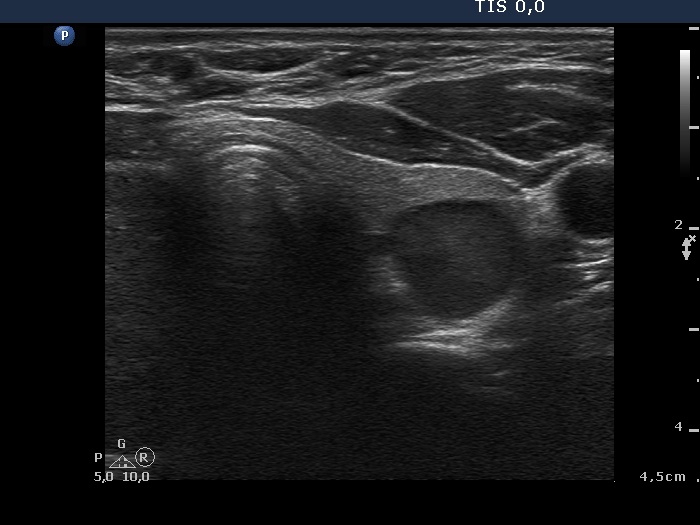

Ultrasonography. The right lobe was moderately hypoechoic while the left was echonormal. A large, less hypoechoic nodule occupied almost the entire right lobe. The nodule presented many hyperechogenic granules and line which corresponded to fibrosis. There were multiple small hypoechogenic lesions in the left lobe.